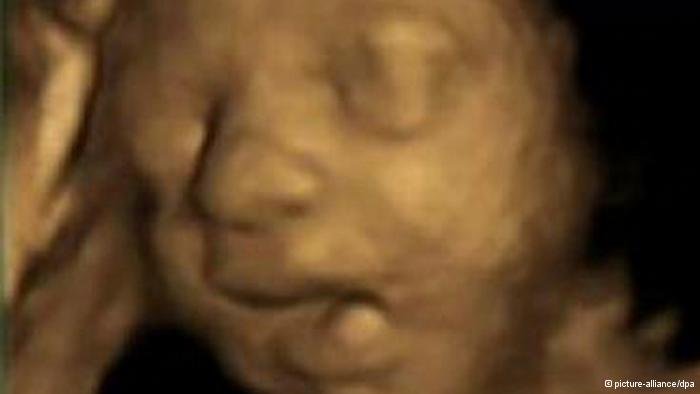

سفر اوباما به جنوب شرقی آسیا، حراج عصا و کلاه چارلی چاپلین، آتش بس در غزه، پرواز خلبانان خوابآلود، اجلاس دی ۸ ، خمیازه جنین و تصاویر دستچین دیگری از رویدادهای جهان در هفتهای که گذشت.

خمیازه را باور کنیم؟

اینترنت ندیده. نه تنها خمیازه را باور داشته باش، همینطور به ادرار جنین در رحم و دیگر کارهای دیگرش مثل سکسکه، و....و....و......